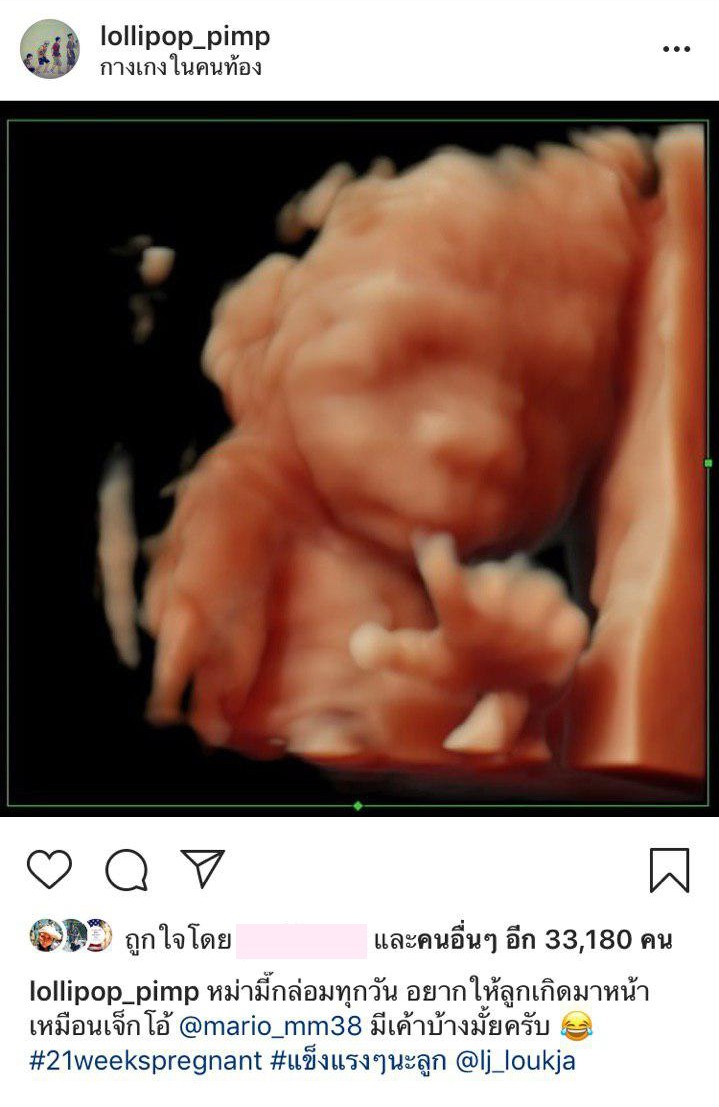

แต่งงานกันมานานกว่า 3 ปี ก็เพิ่งจะมีข่าวดีเรื่องเบบี๋เมื่อไม่นานมานี้ สำหรับคู่ของดีเจหนุ่มอารมณ์ดี ดีเจเผือก พงศธร และภรรยาสาวนอกวงการ ลูกจ๋า วรินทรา ล่าสุดเมื่อวันที่ 11 มกราคม 2562ที่ผ่านมา ดีเจเผือก ก็เห่อลูกคนแรกไม่น้อย เผยภาพอัลตราซาวด์ลูกในวัย 21 สัปดาห์ หรือประมาณ 5 เดือน ซึ่งเริ่มเห็นเค้าโครงหน้าตาชัดเจนขึ้นมากแล้ว

ทั้งนี้ ดีเจเผือกก็บอกอีกว่า ภรรยากล่อมลูกในท้องทุกวัน ว่าอยากให้หน้าตาออกมาเหมือนพระเอกหนุ่มสุดหล่อ มาริโอ้ เมาเร่อ ระบุข้อความว่า “หม่ามี๊กล่อมทุกวัน อยากให้ลูกเกิดมาหน้าเหมือนเจ็กโอ้ @mario_mm38 มีเค้าบ้างไหมครับ #21weekspregnant #แข็งแรง ๆ นะลูก” แต่งานนี้หลายคนกลับมองว่าเบบี๋ตัวน้อยหน้าเหมือนคุณพ่อสุด ๆ โดยเฉพาะจมูกสำเนาถูกต้องเป๊ะ